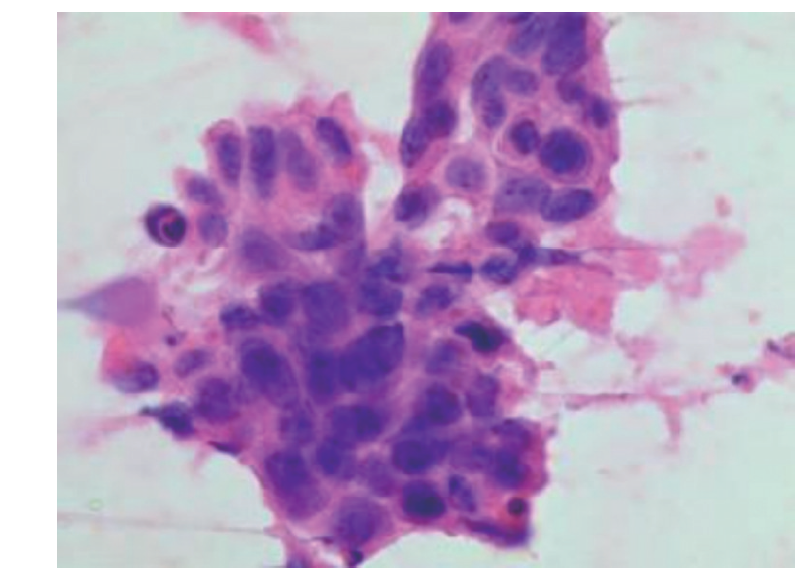

Shindo M, Yoshida Y, Tominaga K, et al. Skin metastasis of hypopharyngeal carcinoma to the nasal tip[J]. Yonago Acta Med, 2013, 56(2): 57-58.

Lopes Alexandre P, Matos R, Marques A, et al. Clown nose: a rare hypopharyngeal cancer metastasis[J]. Ear Nose Throat J, 2022: 1455613211069349. DOI: 10.1177/01455613211069349.

Kocak Z, Uygun K, Uzal MC, et al. Unusual metastatic site in a case of carcinoma of the hypopharynx: nasal tip[J]. J Otolaryngol, 2005, 34(4): 250-252. DOI: 10.2310/7070.2005.34409.